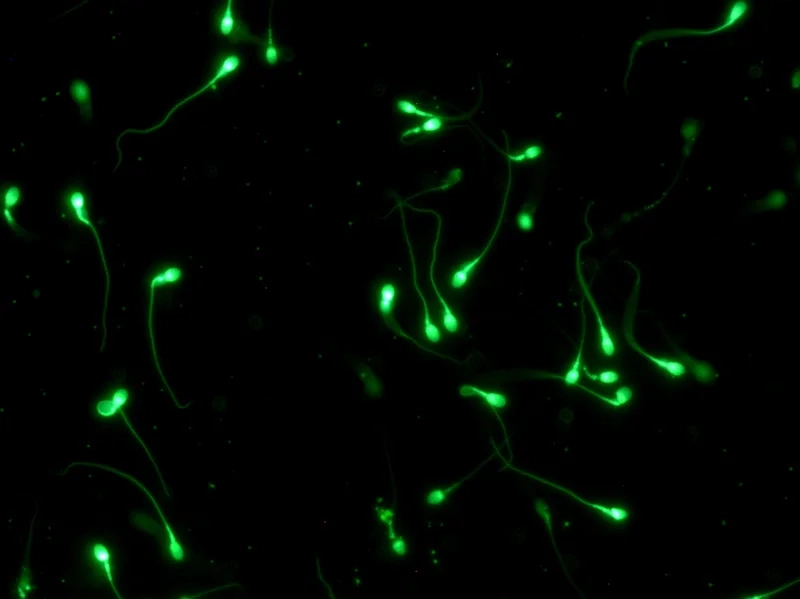

Cấu tạo của tinh trùng dưới kính hiển vi được chia thành ba phần chính: đầu, cổ và đuôi. Phần đầu chứa nhân và enzyme acrosome, cần thiết cho quá trình thụ tinh. Phần đuôi dài và mảnh giúp tạo ra chuyển động để di chuyển về phía trứng.

Chức năng của tinh trùng dưới kính hiển vi là vận chuyển vật chất di truyền của nam giới tới trứng, và tinh trùng di động tốt là yếu tố then chốt quyết định khả năng thụ thai tự nhiên hay trong kỹ thuật tinh trùng ICSI.

Khám phá những hình ảnh tinh trùng dưới kính hiển vi trong bộ sưu tập này sẽ cho thấy sự khác biệt rõ rệt giữa hình thái tinh trùng bình thường với tinh trùng dị dạng.